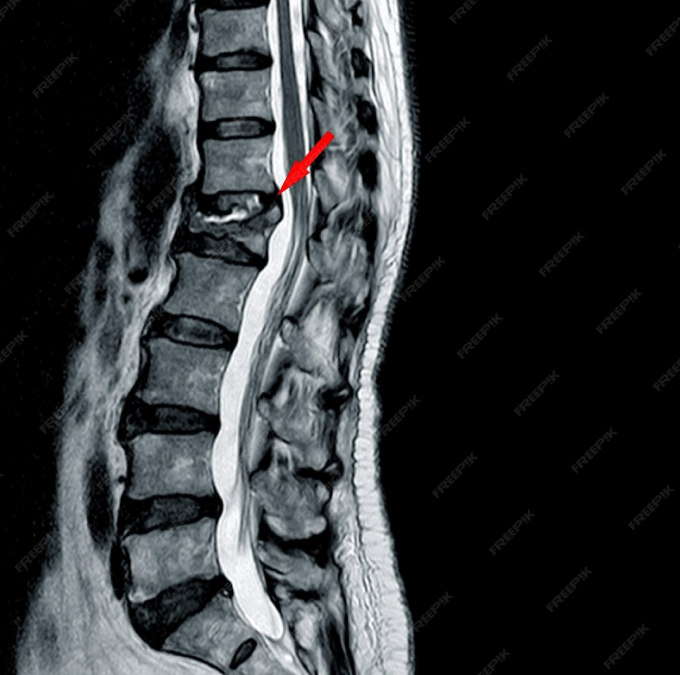

Sırt Fıtığı Nedir? Sırt fıtığı, omurganın torakal bölgesindeki (göğüs kısmı) omurlar arasında yer alan disklerin, dış çeperinin yırtılmasıyla iç kısmındaki jelimsi maddenin dışarı çıkarak omurilik veya sinir köklerine baskı yapması durumudur. Sırt fıtığı, bel ve...